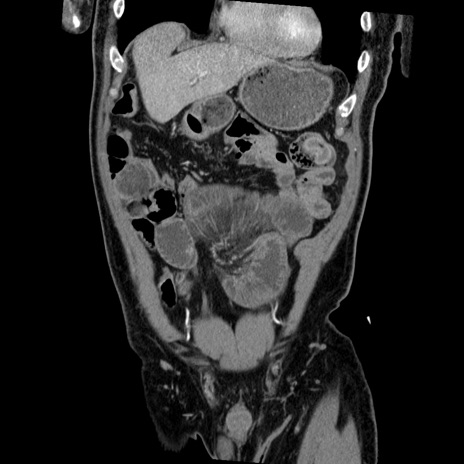

横断像

【症例】50歳代男性

【主訴】腹痛

【現病歴】AVMからの被殻出血のため回復期リハ病棟入院中。 本日午後3時頃急に下腹部痛が出現した。

【既往歴】AVM、被殻出血、虫垂炎、高血圧

【身体所見】意識晴明、左半身不全麻痺、会話の理解は良好、36.5°C、腹部:膨隆、全体に板状硬、下腹部正中に圧痛点あり、反跳痛-、筋性防御不明、右下腹部にope scar

【データ】WBC 9400、CRP 0.06